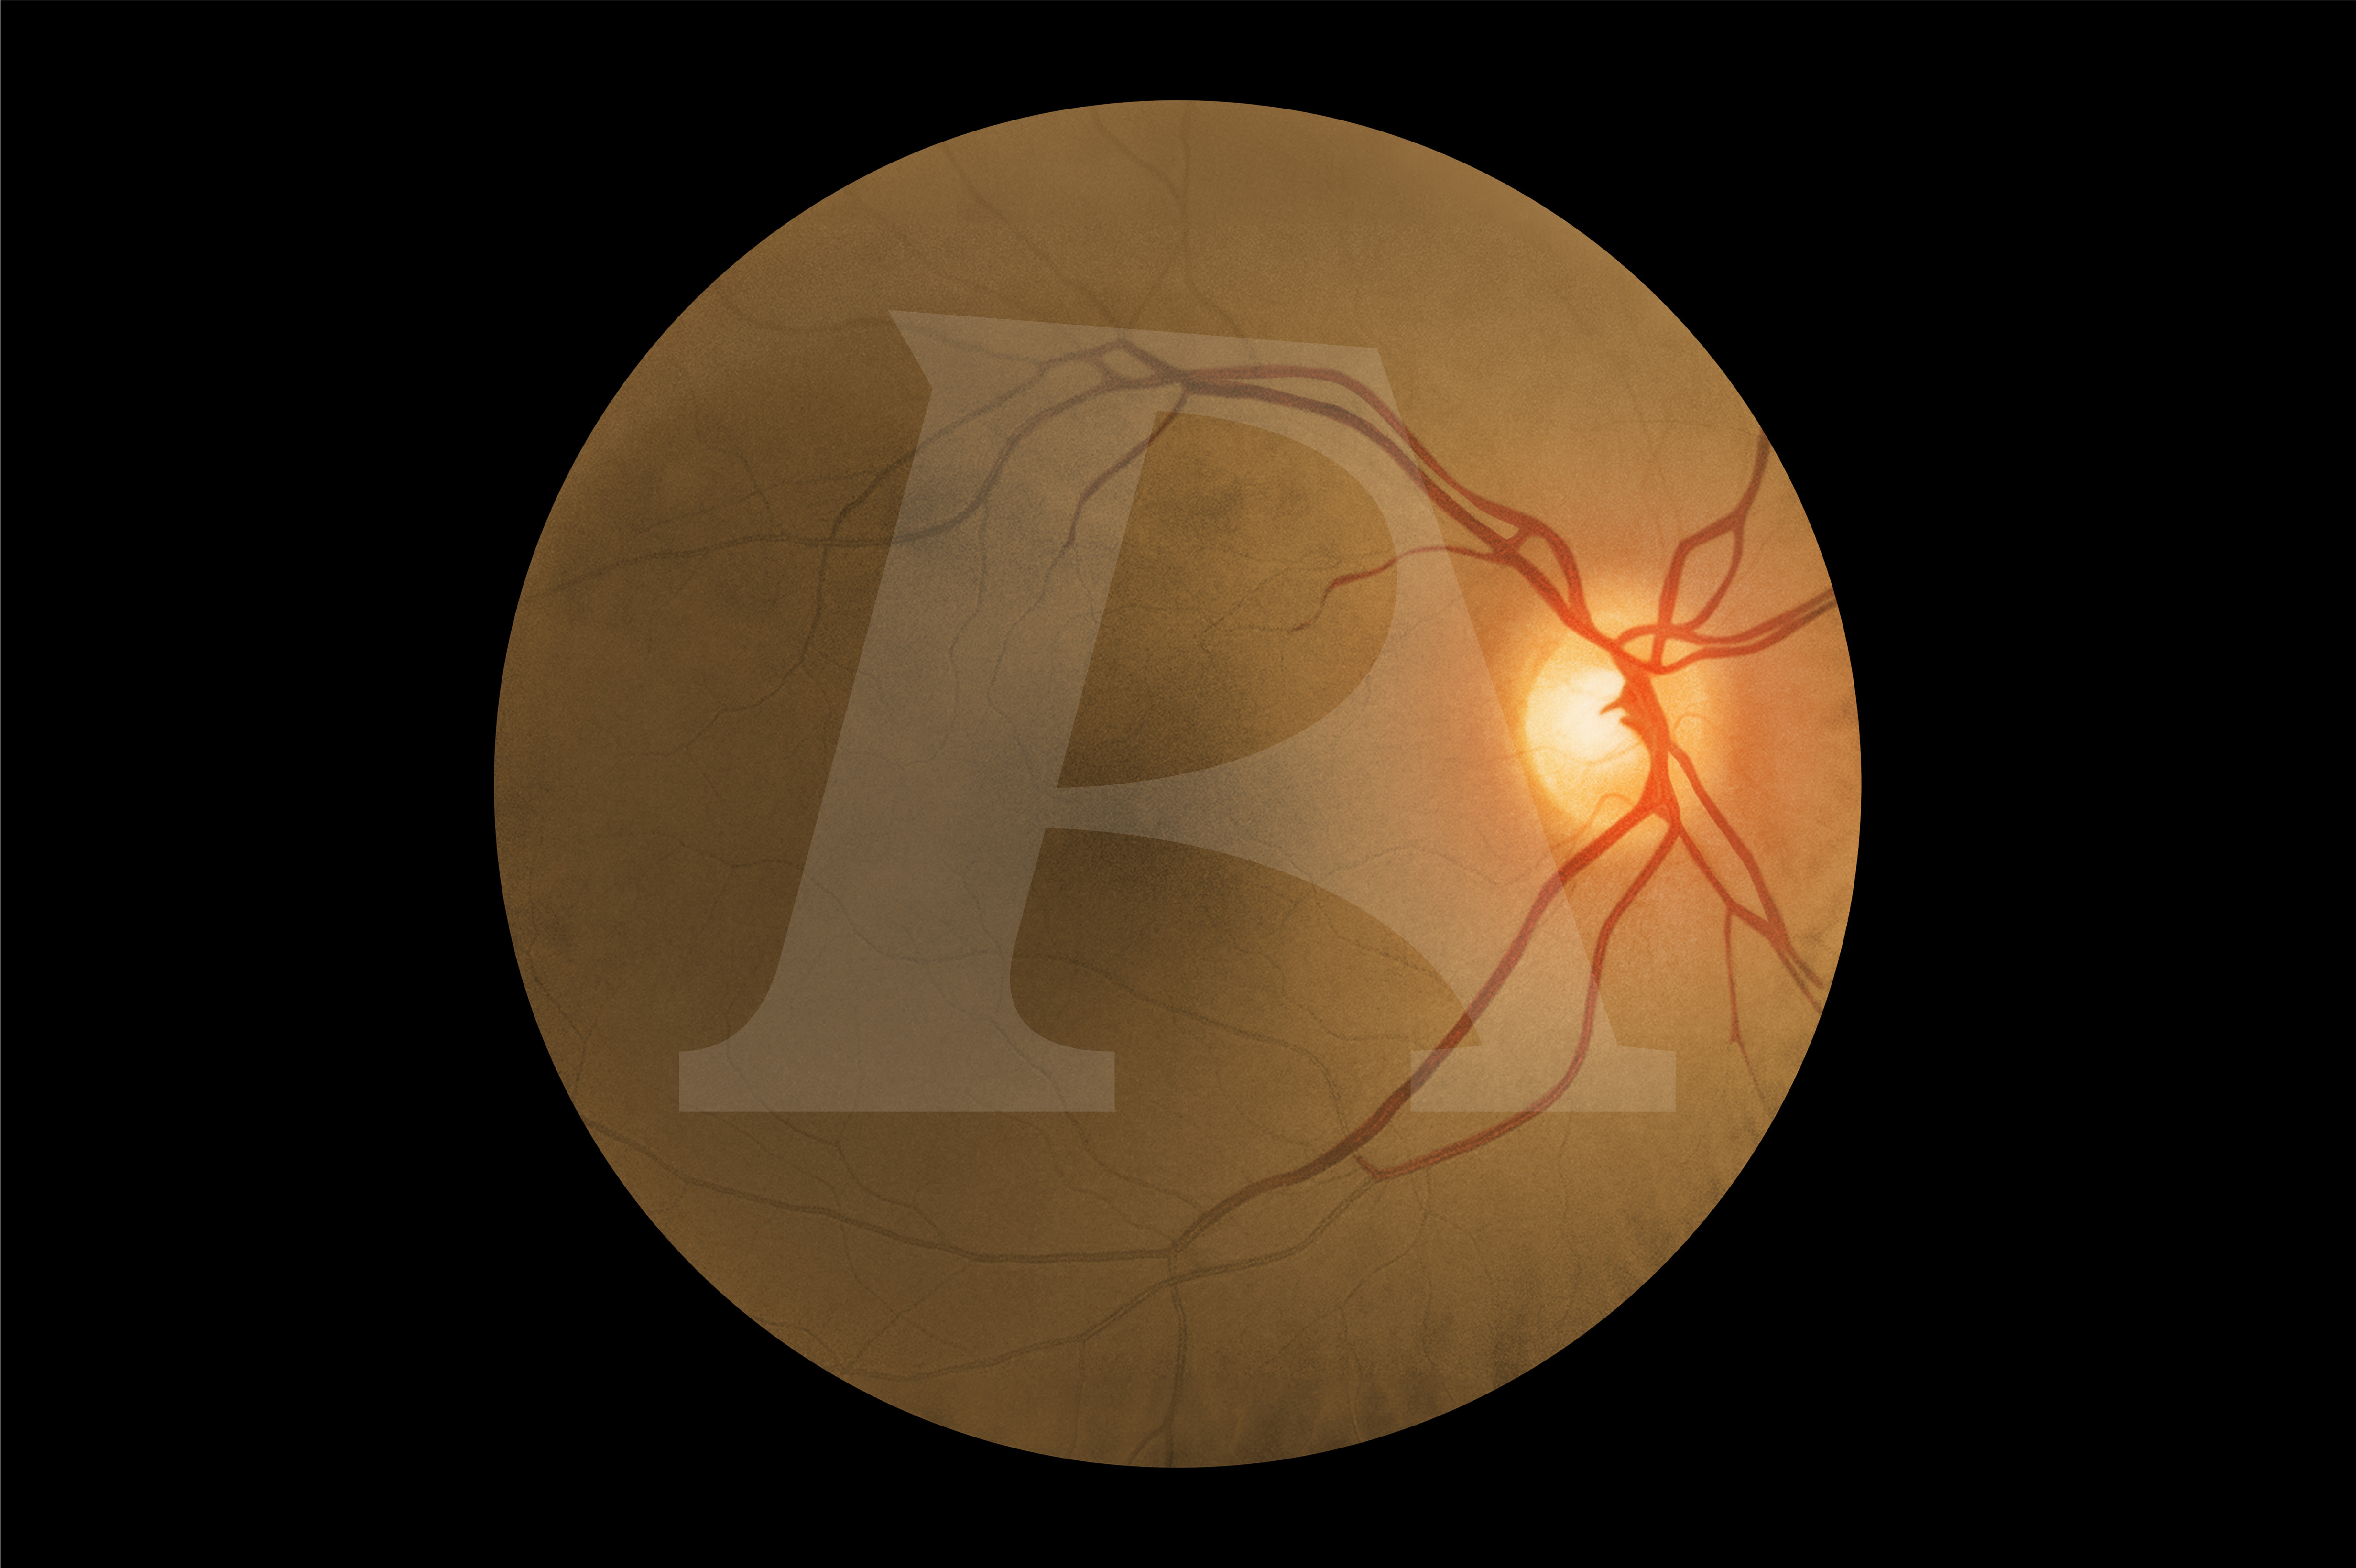

For the first time, advanced digital technology allows trainees to experience how the same eye condition can present differently in patients with light and dark skin tones. In darker-skinned patients, deeper pigmentation in the fundus reduces vessel visibility, a nuance replicated only in the AR503/50 Dark model. This provides learners with invaluable exposure to the clinical variations they will encounter in real practice, enhancing both competence and confidence. Offering two product versions enables trainees to gain an awareness of these visible variances.

Eye conditions and diseases presented digitally for the light skin toned patients AR503 and dark skin toned patients AR503/50:

Diabetic Retinopathy:

Background Diabetic Retinopathy (R1) with Maculopathy (M0)

Important / Common Retinal Conditions:

Normal Fundus (Optic Disc and Retina)